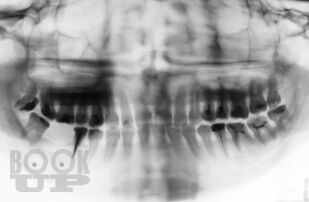

В учебном пособии на современном исследовательском уровне обобщены и подробно изложенылечение и профилактика заболеваний пародонта. Схемы этиопатогенетического лечения заболеваний пародонта постоянно совершенствуются и с успехом используются на протяжении многих лет на кафедре терапевтической стоматологии и в поликлиниках города. Авторы надеются, что издание поможет врачам-стоматологам, а также врачам других специальностей в назначении комплексного, индивидуализированного, этиопатогенетического лечения заболеваний пародонта.